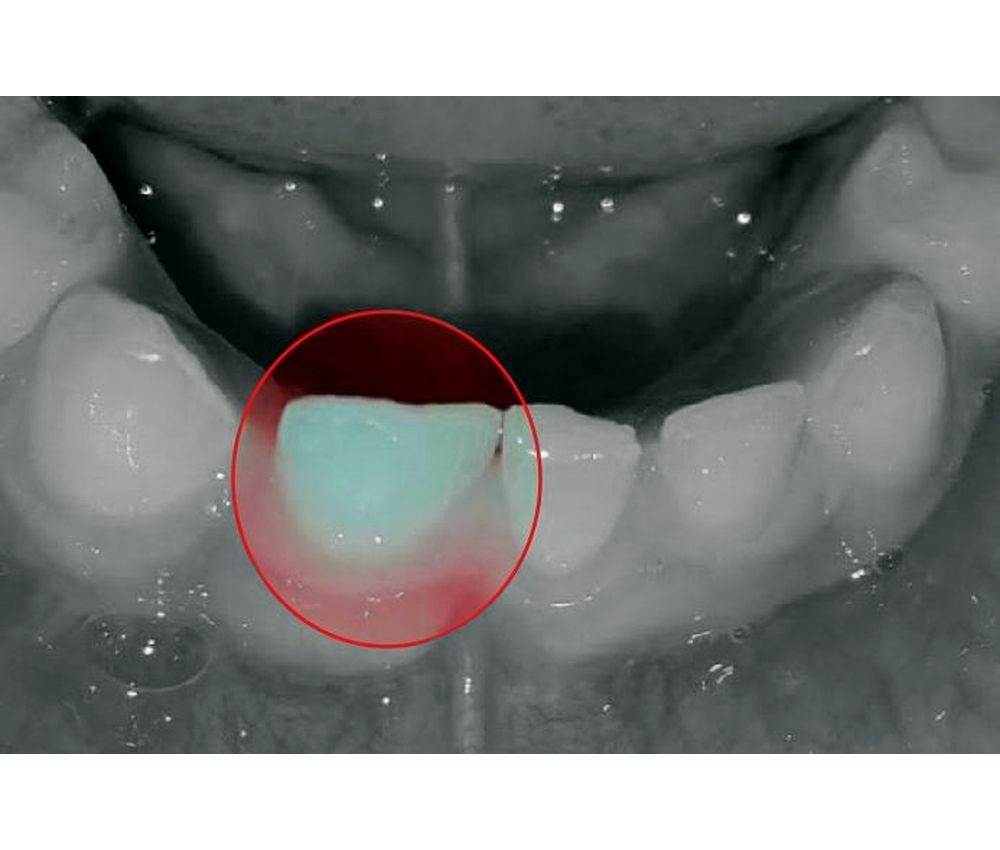

Anomalías dentarias de unión Fusión y Geminación en dentición primaria Fort Union Dental See their team of dentists, read patient reviews, make an. If you are feeling a. At fort union family dental, our dentists in sandy, ut strive to help you smile more!. 418 likes · 1 talking about this · 222 were here. Schedule an appointment today for a healthy smile! Whether you need a dentist to clean your teeth or. Fort Union Dental.